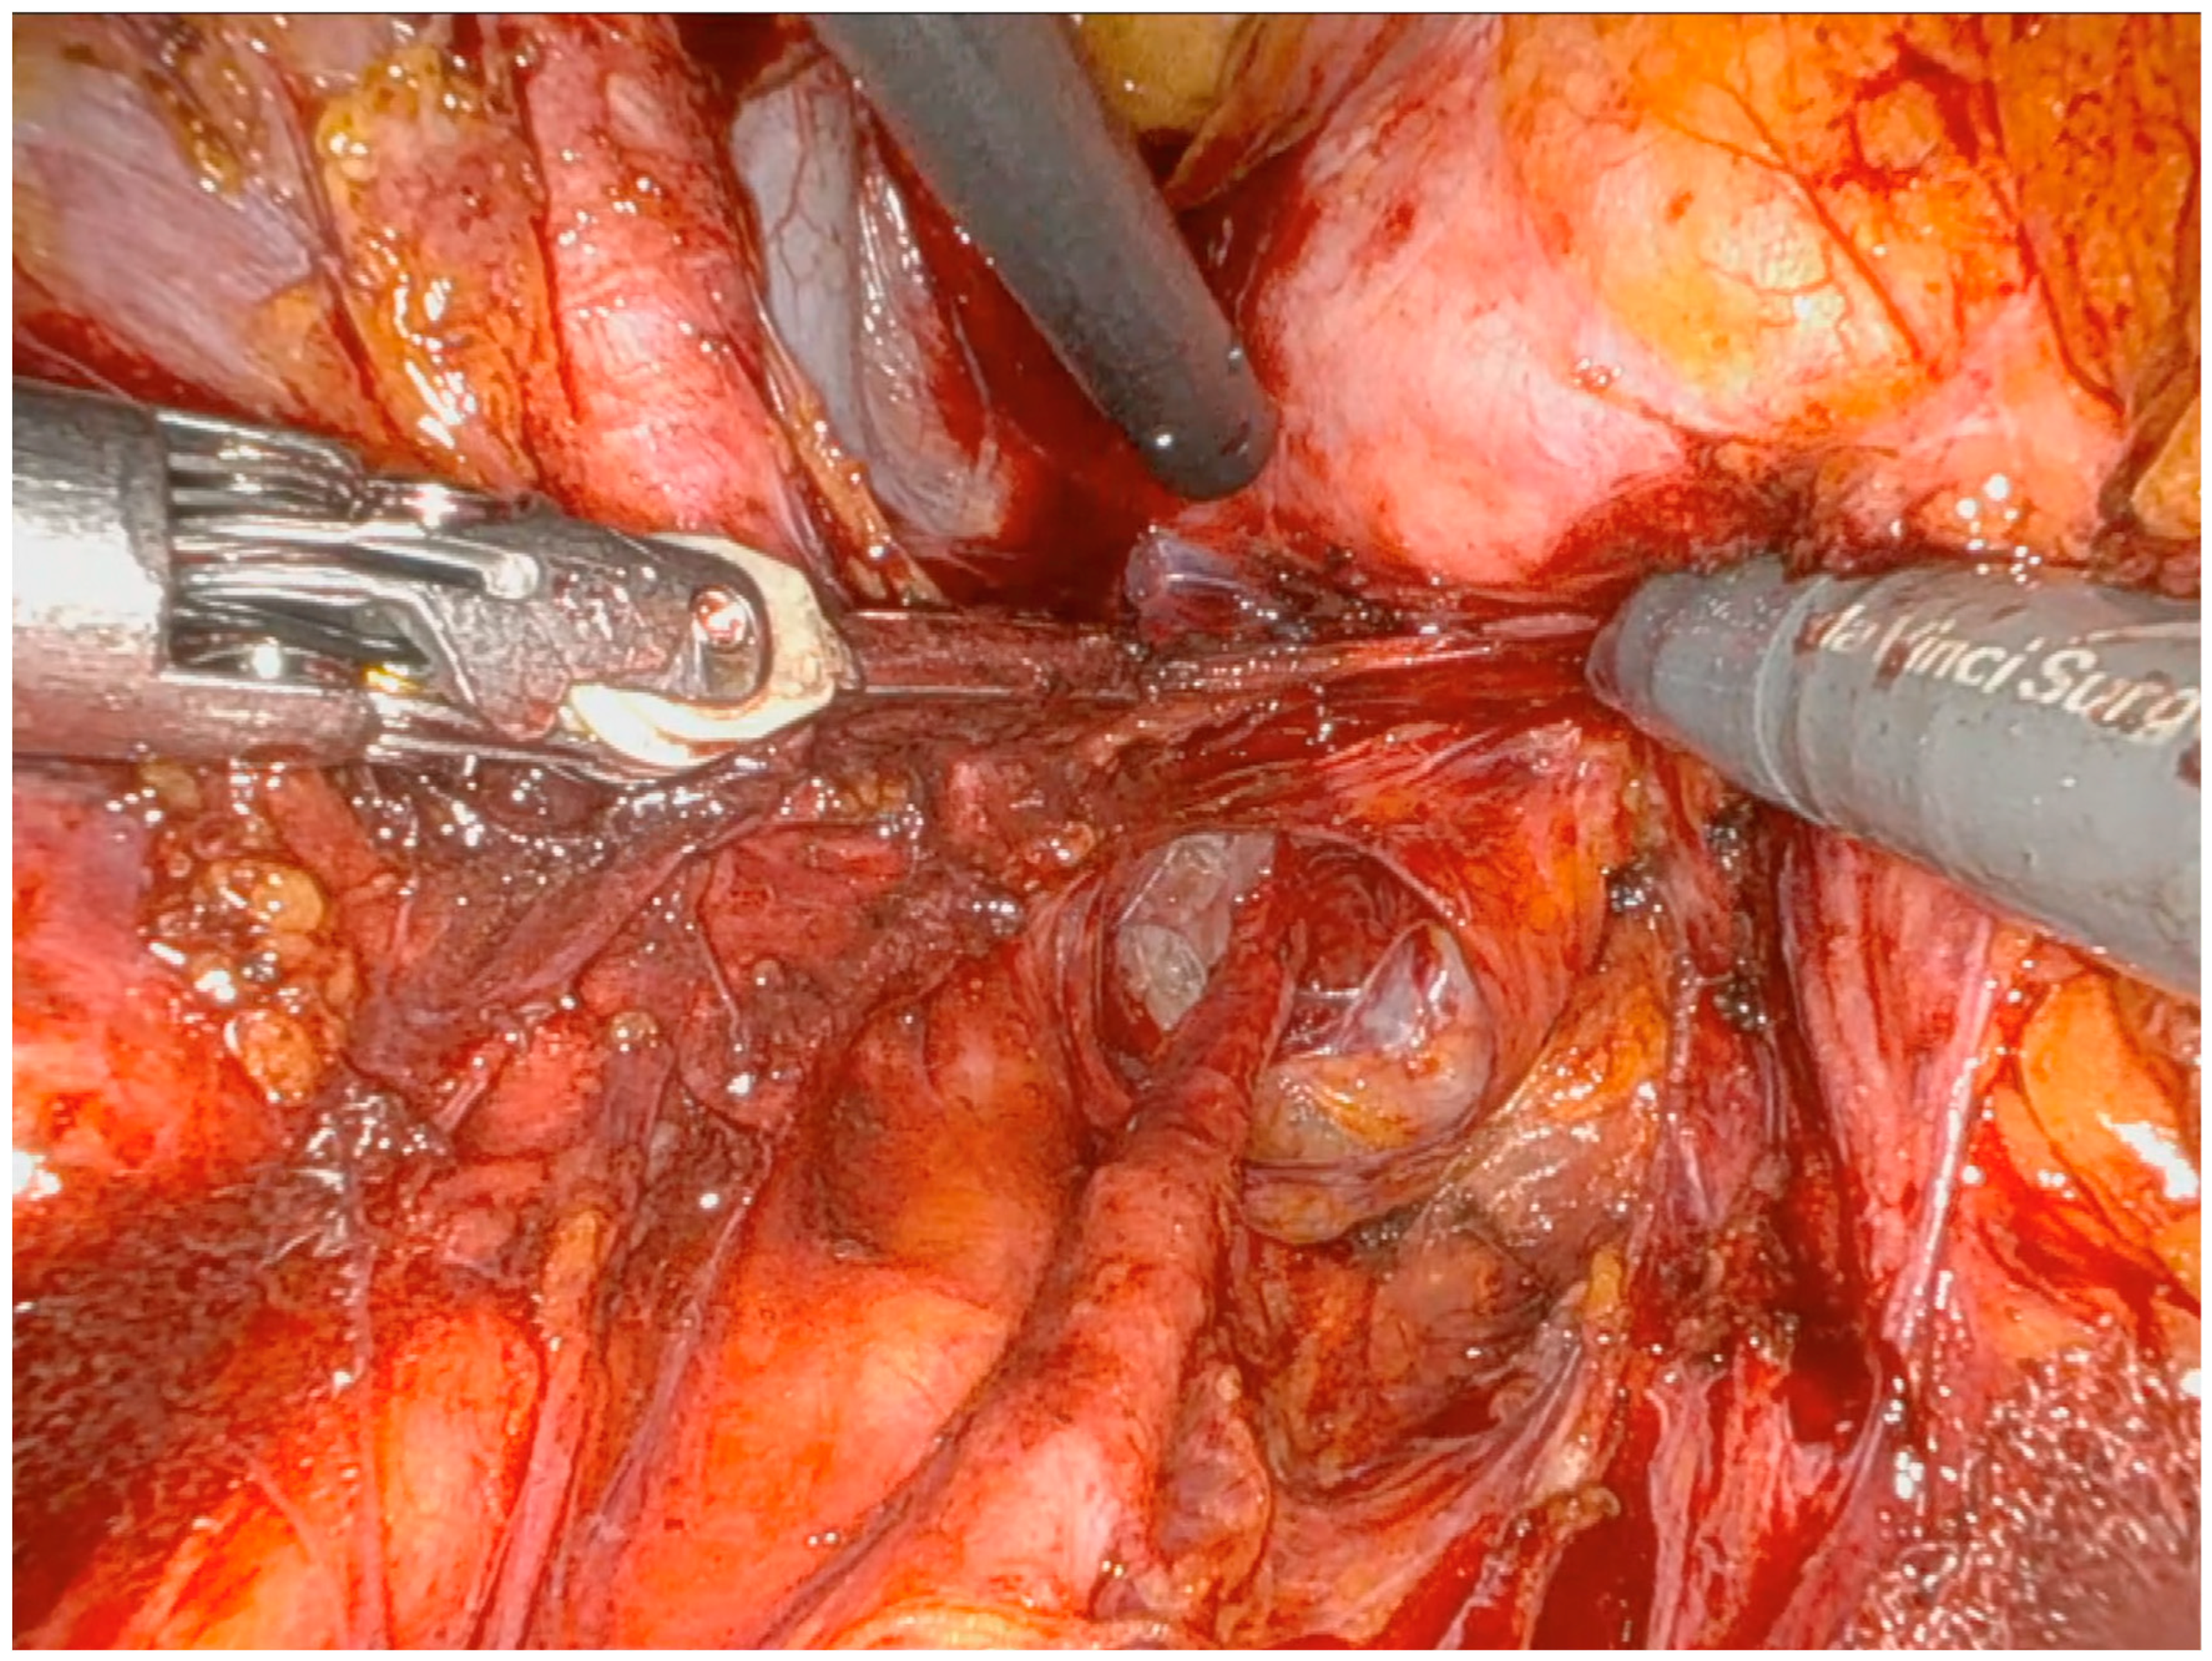

Operative Technique